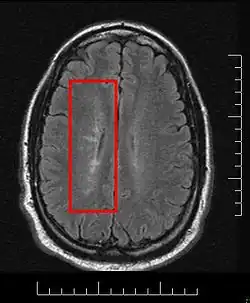

Multiple sclerosis is considered a disease of the white matter because normally lesions appear in this area, but it is also possible to find some of them in the grey matter.[30]

Using high field MRI system, with several variants several areas show lesions, and can be spacially classified in infratentorial, callosal, juxtacortical, periventricular, and other white matter areas.[31] Other authors simplify this in three regions: intracortical, mixed gray-white matter, and juxtacortical.[32] Others classify them as hippocampal, cortical, and WM lesions,[33] and finally, others give seven areas: intracortical, mixed white matter-gray matter, juxtacortical, deep gray matter, periventricular white matter, deep white matter, and infratentorial lesions.[34] The distribution of the lesions could be linked to the clinical evolution[35]

Due to the distribution of the lesions, since 1916 they are also known as Dawson's fingers.[40] They appear around the brain blood vessels.